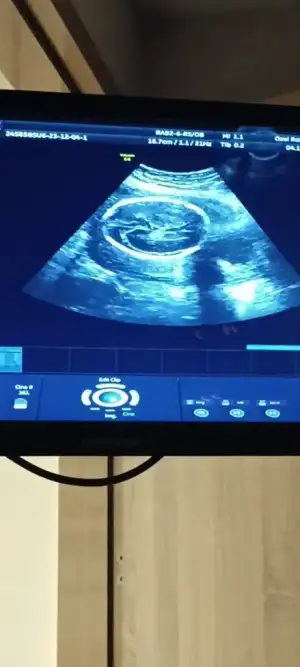

Ben elimden geleni yapayim da eğer olmazsa da sağlık olsun keşke şunu yapsaydim demek istemiyorumBen yürümekte zorlanıyorum yaa kasılma oluyor yürürken hareketlerim baya kisitlanmaya başladı yere düşen şeyi alirken falan çok sıkışıyorum falanilk gebelikte ama at gibiydim yerimde durmazdim